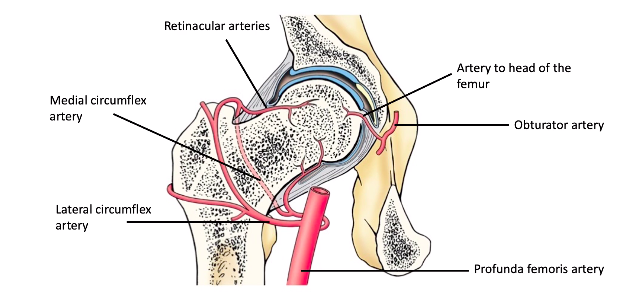

name for the ligament within the hip joint capsule? [1]

ligamentum teres [1]

Hip stability is due to: ? [7]

- Deep insertion of femoral head into acetabulum

- Strong tight articular capsule, this is loose in shoulder. Attaches to greater trochanter and neck of the femur, so is a very tight fit. Gives stability yet also restricts movement

- Ligaments around the joint capsule (especially anteriorly) which will help stabilise the hip joint in extension (the anterior ligaments).

- Large powerful muscles around joint: single, individual most powerful muscle in the body is the gluteus maximus, and the most powerful group of muscles (quadriceps) all work to stabilise the hip joint

- Ligament within articular capsule, ligamentum teres. This attaches the head of the femur to the acetabulum and acts as like a tether. Can also be called ‘ligament of the head of the femur’.

- Fat pad fills central region and adds cushioning for thinnest part of acetabulum. Also helps to keep these two bones together

- Acetabulur labrum is a fibrocartilaginous ring that helps with suction of the femur into the acetabulum. Doesn’t really add to the surface area, 10%, but acts with the synovial fluid to suction the head of the femur into the acetabulum

which is the strongest ligament around the hip joint articular capsule, which strengthens the joint? [1]

how does it achieve this stability? [1]

- anterior iliofemoral ligament - makes anterior side more stable than posterior

- relaxed in flexion but taught in extension

when the hip is extended, what happens to the ligament fibres? [1]

what does this do the the femur & acetabulum? [1]

when the hip is extended, what happens to the ligament fibres? [1]

- fibres become twisted and extended (& tighten)

what does this do the the femur & acetabulum? [1]

ligaments pull head of femur & acetabulum closer

what is blood supply to the head of femur like?

which is main blood supply from?

which is main blood supply from: retinacular artery